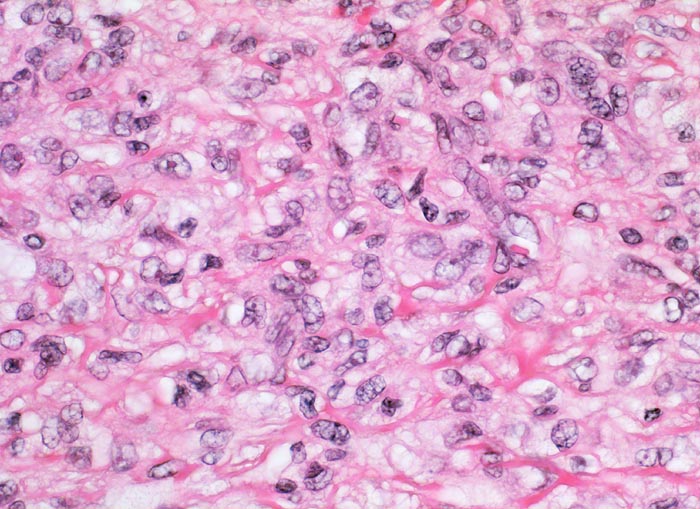

Die Epidermis über dem dermal lokalisierten Tumor zeigt eine Hyperplasie (> 7793) oftmals mit basaler Hyperpigmentierung PathoPic 7803. Histologisch besteht das Histiozytom aus einem Spektrum von Zelltypen mit Merkmalen von dermal dendritischen Zellen, (Myo)fibroblasten und Histiozyten. Zusätzlich können Entzündungszellen, fettspeichernde Tumorzellen mit schaumigem Zytoplasma, eisenpigment (Hämosiderin) speichernde Tumorzellen (> 7718) oder mehrkernige Riesenzellen vorhanden sein. Charakteristisch ist eine wirblige/sternförmige Anordnung von Spindelzellen und Kollagenfasern (=storiformes Wachstumsmuster). Kollagengehalt (> 219) und Zellgehalt (> 3967) sind von Tumor zu Tumor sehr unterschiedlich. Frühe Läsionen sind zell- und gefässreich, spätere zeigen eine vermehrte Fibrosierung und als Folge von Einblutungen Ansammlungen von lipid- und pigmentspeichernden Tumorzellen. Histiozytome können sehr zellreich (> 3968) oder sehr zellarm sein. Sehr charakteristisch ist die unscharfe Begrenzung des Tumors zum dermalen Bindegewebe mit Einschluss kompakter Kollagenfasern innerhalb des Tumors und Ausbreitung von einzelnen Tumorzellen zwischen die tumorangrenzenden Kollagenfasern.

• Tumor bestehend aus spindeligen (myo)fibroblastären Zellen mit länglichen Kernen in unregelmässiger Anordnung (Zellen mit unterschiedlicher Ausrichtung zueinander), mit storiformer (sternförmig/wirbelförmig) oder faszikulärer (parallel ausgerichtete Zellbündel) Architektur.

• Unterschiedliche Zelltypen: fettspeichernde Zellen mit schaumigem Zytoplasma, hämosiderinspeichernde Zellen mit gelbbraunen Pigmentablagerungen im Zytoplasma, mehrkernige Riesenzellen vom Touton Typ, Lymphozyten, spindelzellige (Myo-)fibroblasten und dermal dendritische Zellen (Myofibroblasten und dermal dendritische Zellen sind im Lichtmikroskop nicht unterscheidbar).